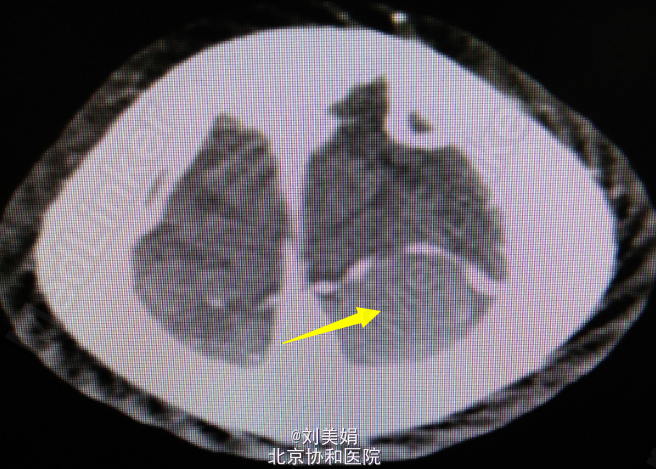

头增强CT:平扫图象显示:左侧顶部见一圆形略高密度影,边缘光整,边界清晰,大小约28.2mm×23.7mm,CT 值 68.2Hu,其内未见钙化,周围脑回受压、塌陷,脑室系统无扩大,脑沟裂未见增宽。中线结构未见明显移位。 增强图象显示:病灶明显均匀强化。CT 值为 92Hu,密度均匀,边缘清晰。右侧筛窦密度增高。